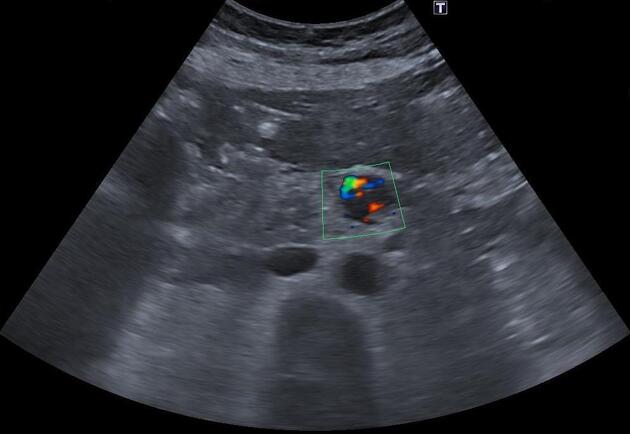

Ультразвуковое исследование при инсулиноме выявляет следующие анатомические признаки:

В серошкальном режиме определяется гипоэхогенное или изоэхогенное образование округлой формы в проекции поджелудочной железы.

В режиме цветового допплеровского картирования выявляется усиленный кровоток в опухоли, соответствующий гиперваскуляризации.

В режиме энергетического допплера визуализируется внутритканевая сосудистая сеть и васкуляризация окружающей ткани.

- Допплеровские режимы позволяют выявить усиленный кровоток, характерный для нейроэндокринных опухолей.